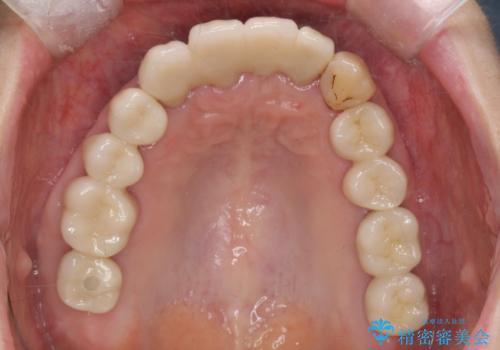

インプラント治療に加え、歯周病に対しての再生治療や歯周ポケットの除去を行う歯周外科、矯正治療、と必要な治療は多岐に渡りましたが、最終的に安定した噛み合わせを得られたとともに、清掃のしやすい口腔内環境を確立できました。